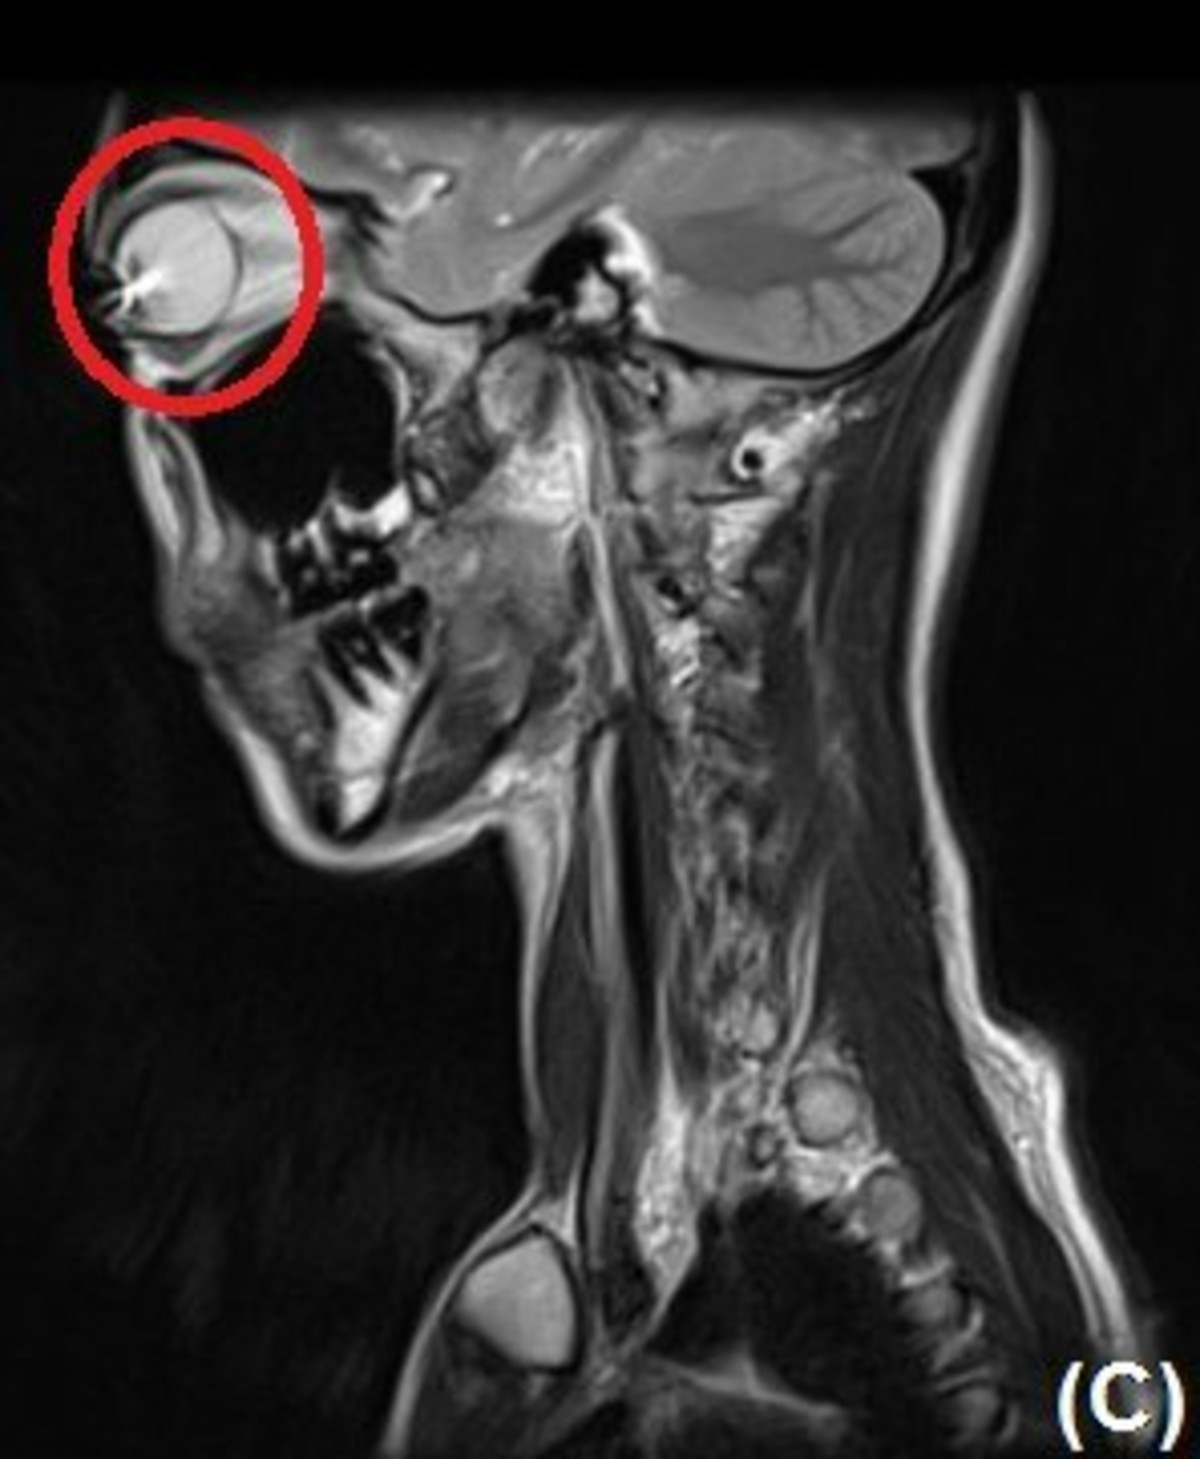

意外と知られていないのか、カラコンしながらMRIは撮れません。そのためか「ケースがない!」という人がいます。再利用するならケースを持ってきて下さい。カラコンの色がついている所には、酸化鉄や酸化チタンが含まれています。カラコンをつけたままMRIを撮ると、目の表面に傷が付くかもしれません。 ※1

実はカラコンをつけたままのMRIはとても危険です。カラコンの色がついている部分には、酸化鉄、酸化チタンといった金属成分が含まれています。MRIは強力な磁場を使う検査です。そのため、これらの成分が影響を受ける可能性があるのです。そのため、検査直前に外すことになり、「再利用したいのにケースがない」という人が一定数いるそうです。

カラコンをつけたままMRIを撮影すると目の表面に傷が付くおそれがあるとのこと。検査後にまた使いたい人は必ずケースを持参するのがおすすめですよ。